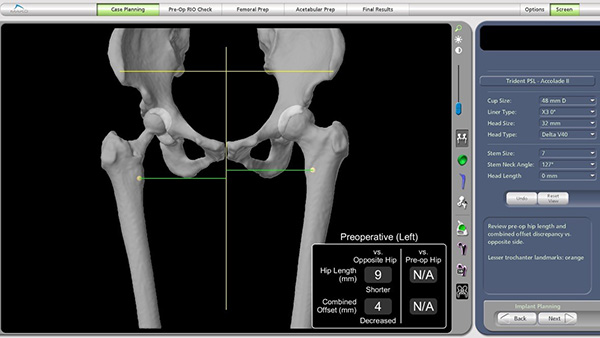

全髋关节置换手术患者最容易出现不满意的表现就是术后双侧下肢不等长,机器人关节置换术通过精准规划可以很大程度上避免这一并发症的出现,而术前规划离不开CT薄层扫描及三维重组技术。为此,放射科副主任燕飞牵头协调,制定了详细的扫描规范。技师长张永县带领技师朱蕾等完成了患者的术前下肢CT扫描,骨科团队基于患者CT影像资料进行三维建模和个体化术前规划,精确确定假体型号、髋臼杯角度和下肢力线,以确保术后肢体长度与功能恢复的最佳匹配。

术前影像显示右髋置换术后状态,左侧肢体较右侧短缩9mm。